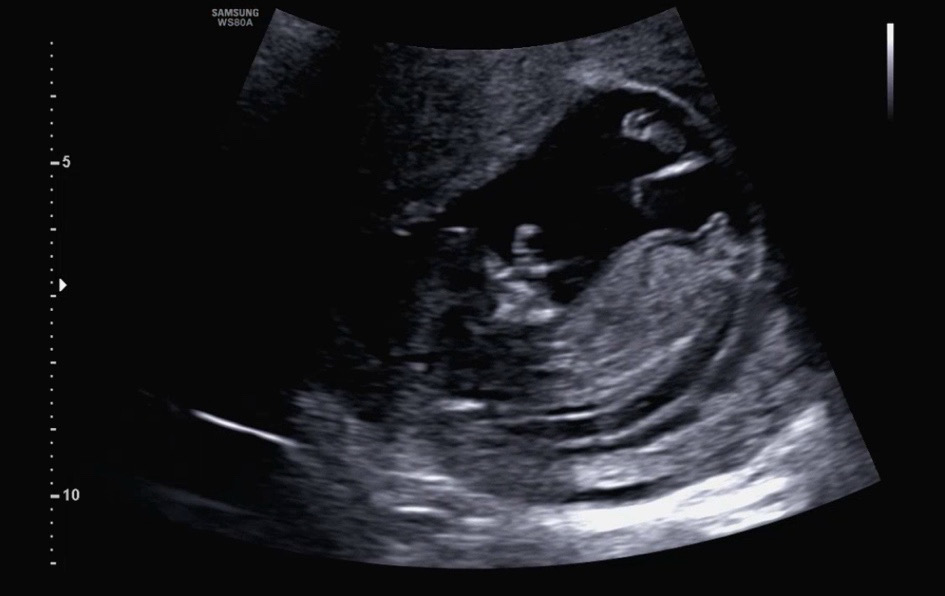

12주 2일차예용 저게 고추인건지 아니면 각도법으로 구분해야하는지 ..ㅠㅠ 전혀 도무지 모르겠..네요…..?

각도법 ..? 고츄 …?